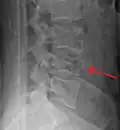

A burst fracture of L4 as seen on plane X ray -